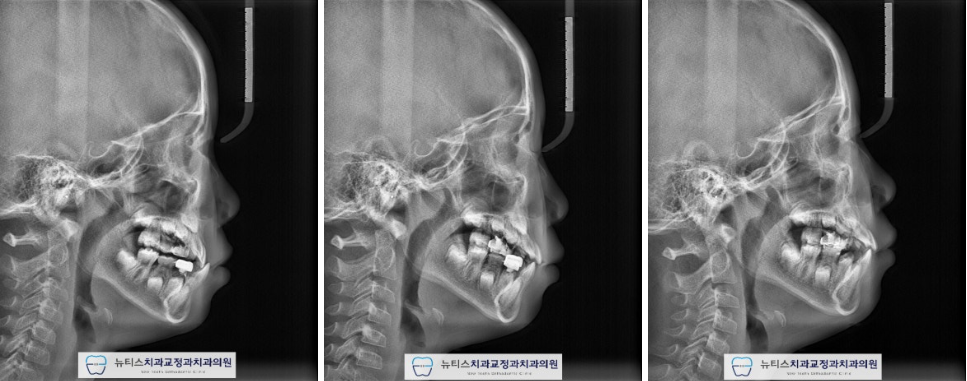

¾È³çÇϼ¼¿ä.ºÎ»ê ±ÝÁ¤±¸ ±¸¼µ¿¿¡ À§Ä¡ÇÑ´ºÆ¼½ºÄ¡°ú±³Á¤°ú Ä¡°úÀÇ¿ø±³Á¤°ú Àü¹®ÀǾȼö¹ü ¿øÀåÀÔ´Ï´Ù. À̹ø ÁÖºÎÅÍ À帶°¡ ½ÃÀ۵ȴٰí ÇÕ´Ï´Ù~Áö³ÁÖ¿¡µµ À帶°¡ ½ÃÀ۵ȴٰí ÇÏ´øµ¥...7¿ùÀº ÈÄ´þÁö±ÙÇÑ ³¯¾¾°¡ À̾îÁö³×¿ä. ÀϱⰡ º¯È¹«»óÇÏ´Ï´Ùµé °Ç° °ü¸® Àß ÇÏ½Ã±æ ¹Ù¶ø´Ï´Ù~ À̹ø¿¡ Æ÷½ºÆÃÇÒ ÄÉÀ̽º´Â"#ºÎ»ê¾î¸°À̹ݴ뱳ÇÕ ÀÔ´Ï´Ù. ¹Ý´ë±³ÇÕÀ» °¡Áö°í ÀÖÀ¸¸é Á¤»óÀûÀÎ ¼ºÀå ¹ßÀ°À» ÇÏÁö ¸øÇÏ¿©ÁÖ°ÆÅÎÀÌ ´õ ½ÉÇØÁú ¼ö ÀÖÀ¸¸ç ºÎÁ¤±³ÇÕÀÌ ¹ß»ýµË´Ï´Ù. ¼ºÀÎÀÇ °æ¿ì ½ÉÇÑ ¹Ý´ë±³ÇÕ Áï, ÁÖ°ÆÅÎÀº ±³Á¤Ä¡·á¸¸À¸·Î ÇØ°áÀÌ ¾î·Á¿ï ¼ö ÀÖÀ¸³ª ¼ºÀå±â ¾î¸°ÀÌÀÇ °æ¿ì¿¡´ÂÁ¤»óÀûÀÎ ¼ºÀå ¹æÇâÀ¸·Î À¯µµÇØ º¼ ¼ö ÀÖ½À´Ï´Ù. À̰¡ Ʋ¾îÁö°í µ¡´Ï°¡ Àְųª °ø°£ÀÌ ¸¹ÀÌ ÀÖ´Â °æ¿ì¿¡´Âº¸È£Àںв²¼ ÀÎÁö°¡ ºü¸£³ªÀÌ·± ºÎÁ¤±³ÇÕ (¹Ý´ë±³ÇÕ) À» °¡Áö°í ÀÖÀ¸¸é Àß ¸ð¸£½Ã´Â °æ¿ì°¡ ¸¹½À´Ï´Ù. ÈçÈ÷ ¾Þ±Û¾¾ 3±Þ ºÎÁ¤±³ÇÕÀ̶ó°í Çϴµ¥À̸¦ ¹æÄ¡ÇÏ°Ô µÇ¸é ³ªÁß¿¡ ¹®Á¦°¡ Å©°Ô µÉ ¼ö ÀÖÀ¸´Ï°¡±ÞÀû ºü¸¥ Á¢±ÙÀÌ ¿ä±¸µË´Ï´Ù.(¾ÆÀÌ º¸Çè¿¡¼ º¸ÀåÇØ ÁÖ´Â °æ¿ìµµ ÀÖ½À´Ï´Ù) #ºÎ»ê¾î¸°À̱³Á¤Ä¡°ú ÀÎ ÀúÈñ ´ºÆ¼½º¿¡¼´Â¼ö¿ÏºÎ (¼Õ»À) ¿¢½º·¹À̸¦ ÅëÇØ¿ì¸® ¾ÆÀÌÀÇ ¼ºÀå ´Ü°è¸¦ ÆÇ´ÜÇÏ¿© °¡Àå ÀûÀýÇÑ ½Ã±â¿¡ Ä¡·á¸¦ ÁøÇàÇÒ ¼ö ÀÖµµ·Ï ÇØ µå¸³´Ï´Ù. À̰¡ ¹Ý´ë·Î ¹°¸°´Ù°í ÇÏ¿©#ºÎ»ê¾î¸°À̱³Á¤Ä¡°ú ÀÎ ÀúÈñ ´ºÆ¼½º·Î³»¿øÇϽŠºÐÀÔ´Ï´Ù.ÃÊÁø »çÁøÀÔ´Ï´Ù.È¥ÇÕÄ¡¿±â ´Ü°è·Î ÇöÀç ¾Õ´Ï°¡ ¹Ý´ë·Î ¹°¸®°í ÀÖ½À´Ï´Ù. ÀÌ·¯ÇÑ #ºÎ»ê¾î¸°À̹ݴ뱳ÇÕ À» º¸ÀÌ´Â °æ¿ì¿¡´ÂÁ¤»óÀûÀÎ ÅÎÀÇ ¼ºÀåÀ» ÀúÇØÇÒ ¼ö ÀÖ½À´Ï´Ù. ¹æ»ç¼± »çÁø¿¡¼µµ¾Õ´ÏÀÇ ¹Ý´ë±³ÇÕÀ» È®ÀÎÇÒ ¼ö ÀÖ½À´Ï´Ù. #ºÎ»ê¾î¸°À̱³Á¤Ä¡°ú ÀÎ ÀúÈñ ´ºÆ¼½º¿¡¼´Â¿©·¯°¡Áö °Ë»ç¸¦ ÅëÇÏ¿© ÇÁ¸®¿Ã¼Ò¶ó´Â ÀåÄ¡¸¦ »ç¿ëÇÏ¿©#ºÎ»ê¾î¸°À̹ݴ뱳ÇÕ À» °³¼±Çϱâ·Î ÇÏ¿´½À´Ï´Ù.  Ä¡·á ÈÄ »çÁøÀÔ´Ï´Ù.

#ºÎ»ê¾î¸°À̹ݴ뱳ÇÕ ÀÌ °³¼±µÇ¾ú°íÀüÄ¡ºÎÀÇ ±³ÇÕ°ü°è°¡ ¾çÈ£ÇØ Á³½À´Ï´Ù. Ä¡·á ÈÄ ¹æ»ç¼± »çÁø¿¡¼µµ¹Ý´ë±³ÇÕÀÌ °³¼±µÈ °ÍÀ¸·Î È®ÀÎÇÒ ¼ö ÀÖ½À´Ï´Ù.(Ä¡·á±â°£ 6°³¿ù)  Ä¡·á Á¾·á ÈÄ 1³â Áö³ »çÁøÀÔ´Ï´Ù. #ºÎ»ê¾î¸°À̱³Á¤Ä¡°ú ÀÎ ÀúÈñ ´ºÆ¼½º¿¡¼´Â¹Ý´ë±³ÇÕÀ» °³¼±ÇÑ ÀÌÈÄ, À¯Áö°¡ Àß µÇ´ÂÁö ´Ù¸¥ ¹®Á¦°¡ ¾ø´ÂÁö ÁÖ±âÀûÀΠüũ¸¦ ½ÃÇàÇÕ´Ï´Ù. ÃÊÁø, Ä¡·á ¸¶¹«¸®, 1³â À¯Áö üũ »çÁøÀÔ´Ï´Ù. Àß À¯Áö°¡ µÇ¾ú°í ÀûÀýÇÑ ½Ã±â°¡ µÇ¸é2Â÷ ±³Á¤À» ÁøÇàÇÒ ¿¹Á¤ÀÔ´Ï´Ù~ #ºÎ»ê¾î¸°À̹ݴ뱳ÇÕ ÀÇ °æ¿ì¿¡´ÂÄ¡·áÀÇ Å¸À̹ÖÀÌ Áß¿äÇϱ⠶§¹®¿¡ Àü¹®°¡¿Í »ó´ãÇÏ´Â °ÍÀÌ Áß¿äÇÕ´Ï´Ù. #ºÎ»ê¾î¸°À̱³Á¤Ä¡°ú ÀÎ ÀúÈñ ´ºÆ¼½º¿¡¼´Â¿ì¸® ¾ÆÀÌ¿¡ ´ëÇÏ¿© ´Ù¾çÇÑ °Ë»ç¸¦ ÅëÇØÃÖÀûÀÇ Ä¡·á ¹æ¹ýÀ» µµ¸ðÇØ µå¸®°í ÀÖ½À´Ï´Ù. Ȥ½Ã ¿ì¸® ¾ÆÀÌÀÇ Ä¡¾Æ°¡ ¹Ý´ë·Î ¹°¸°´Ù´øÁö¾ÕÀ¸·Î »ÀÃÄÁ³´Ù¸é ¾ðÁ¦µçÁö ¸Á¼³ÀÌÁö ¸¶½Ã°íÀúÈñ ´ºÆ¼½º·Î ¿¬¶ô ÁÖ¼¼¿ä~